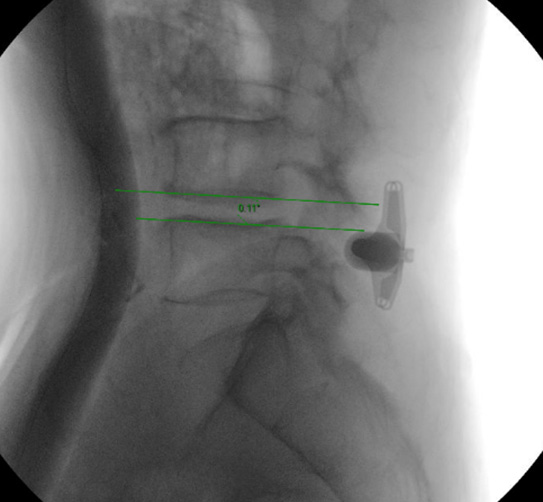

The interspinous device implantation is one of the minimally invasive surgical methods for treating lumbar spinal stenosis. By implanting a specially designed device between the spinous processes of the lumbar spine, the narrow spinal canal can be stretched open to alleviate nerve compression. This type of surgery has minimal trauma and quick postoperative recovery, especially suitable for elderly patients who cannot tolerate major surgery.

Preoperative (left) and postoperative (right) with interspinous device